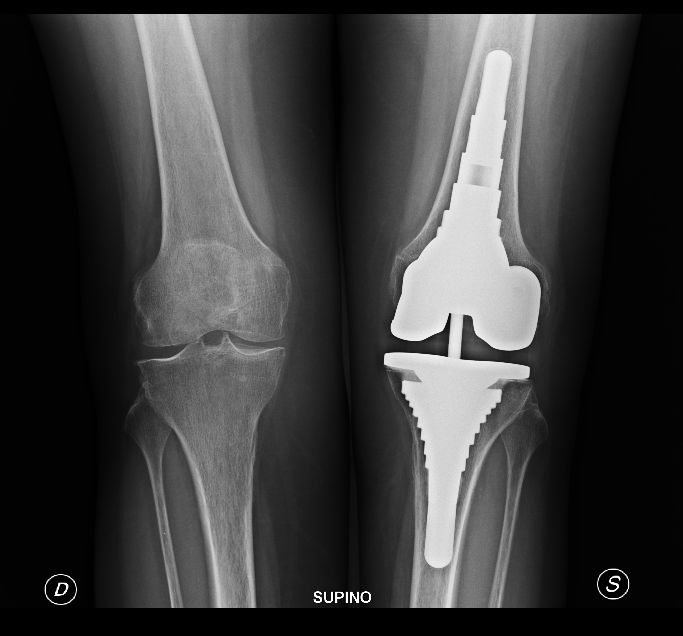

Foto e video